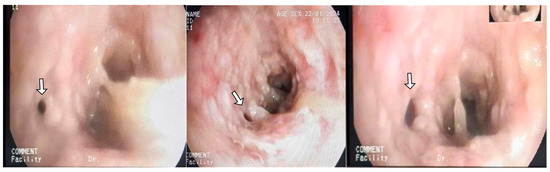

He returned to ED three days later with severe respiratory distress and was immediately transferred to the ICU and intubated due to hypoxia and increased work of breathing. Following intubation, he was hemodynamically stable. Physical examination revealed significantly decreased breath sounds bilaterally. Ventilator waveforms indicated high airway pressure and increased resistance. An urgent bronchoscopy was performed, revealing significant (>75%) narrowing in the main bronchus. Immediate debulking with biopsy forceps in the main bronchus was performed to assist ventilation. Bilateral main bronchi exhibited obstructive tracheobronchitis with prominent mucous plugs (Figure 1) and pseudomembrane (Figure 2). A bedside chest X-ray following intubation showed mild ground-glass opacification in the right lung (Figure 3). The CT scan performed the day after intubation and ICU admission revealed new bilateral patchy opacities and small nodular lesions in the lung parenchyma (Figure S2).

Figure 1. Bronchoscopy performed after intubation in a 36-year-old man with obstructive tracheobronchitis secondary to invasive pulmonary aspergillosis, showing prominent mucous plugs and airway sloughing. (A) Left main bronchus, (B) Major fissure of left bronchus, (C) Right upper Lobe.

Figure 2. Bronchoscopy of basal segments of the left lower lobe, showing thick pseudomembrane with almost complete closure of anterior basal segment (white arrow).